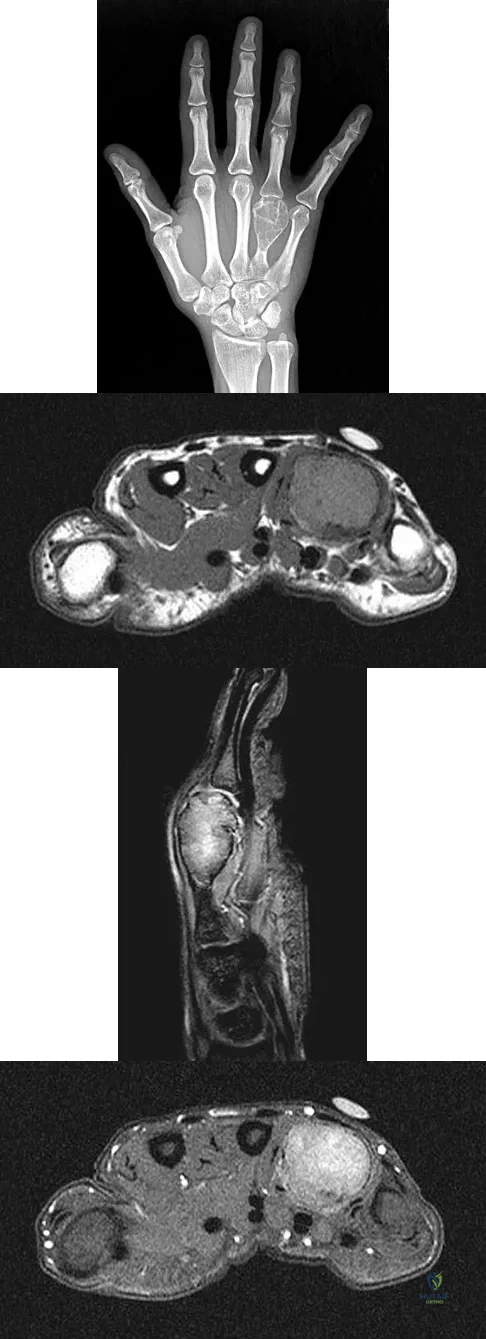

Question 94

A 26-year-old man has had hand pain and progressive swelling in the knuckle for the past several months. He denies any trauma to the hand. The ring finger metacarpophalangeal joint is tender, and there is loss of motion in the digit. Figure 32a shows the radiograph and Figures 32b through 32d show the T1-weighted, T2-weighted, and gadolinium MRI scans, respectively. What is the most likely diagnosis?

Explanation